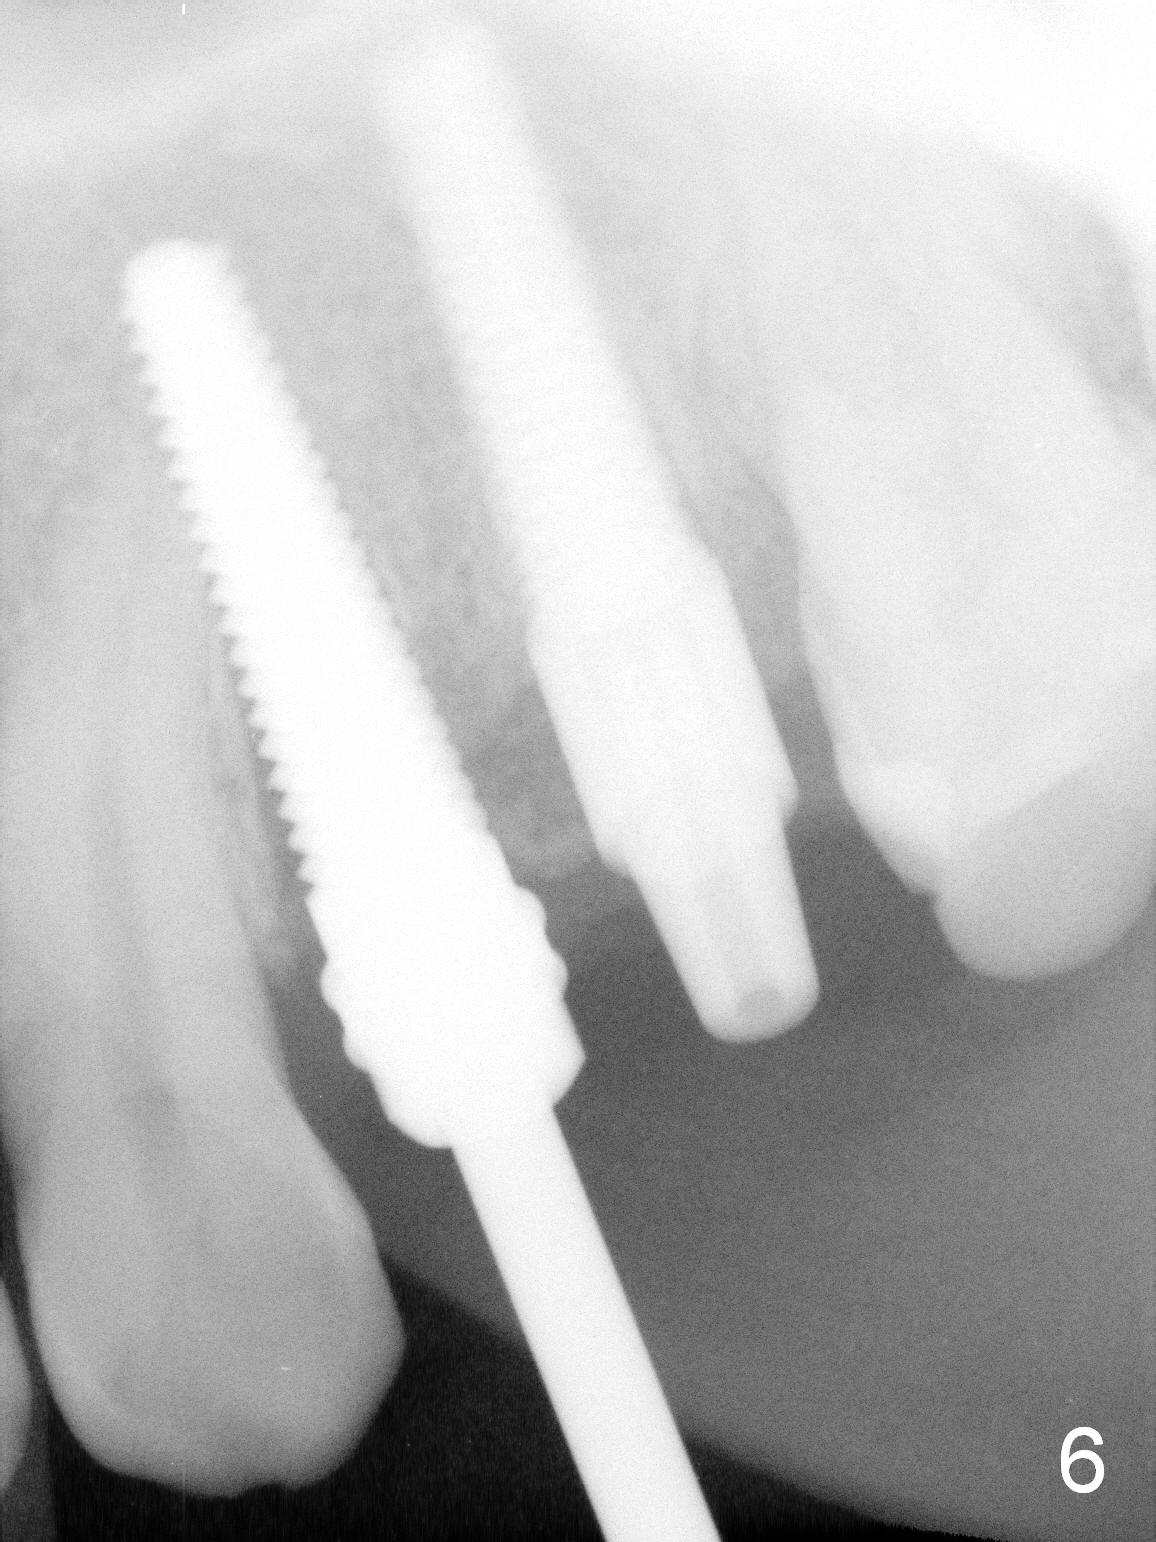

Taking 2 additional PAs with sensor 1 is frustrating (Fig.1,2), no apices shown.  Osteotomy is done smoothly with 2 mm pilot drill at 20 mm, 2.5 mm reamer at 17 mm, and 3 mm reamer at 14 mm and 4.5x20 mm tap at 17 mm.  The 1st intraop PA is taken with sensor 1 when 2 of 4.5x20 mm implants are placed (Fig.3); the implant at #12 is close to the root of the tooth #11.  The 2nd PA is taken with sensor 2: the apex of #11 touches the implant at #12 (Fig.4).  There is no separation when panoramic X-ray is taken (Fig.5).  Effort is exerted to re-direct the osteotomy twice (Fig.6: tap; Fig.7: implant) without success.  When the implant is removed, a PA is taken; it appears that the root of the tooth #11 has no damage (Fig.8).  To obtain the best recovery, socket preservation is carried out with 50/50 cortical/cancellous allograft mixed with Osteogen (Fig.12 *) and Collagen Dressing (Fig.9: #12).  A 2 (or 3)-unit provisional bridge (Fig.10: #12,13) is fabricated over the implant (Fig.9 I)/abutment (A) to cover these 2 sockets.  After acid etching #11 D surface (Fig.9 >) and relining (Fig.11 *), the provisional bridge is bonded to the tooth #11 (Fig.11,12 black >) so that bone graft will be less likely dislodged.